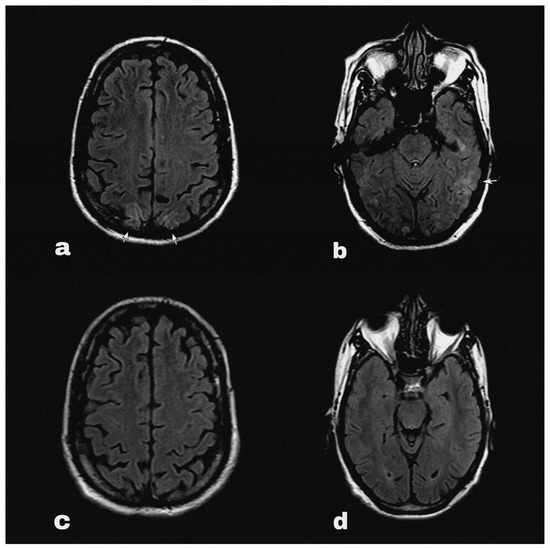

At some point his symptoms persisted overnight at home, and on the following morning he had an episode of generalised tonic clonic seizure followed by altered sensorium. He was immediately brought to the emergency department, where his blood pressure was 200/100 mmHg. His sensorium was altered with a Glasgow Coma Scale of 9/15 points. He did not report fever, visual disturbances or any sensory symptoms. The routine blood reports, including complete blood count and renal and liver function tests, along with routine urine tests did not reveal abnormalities except hyponatraemia (serum Na 127 mEq/L). An HIV test was negative during his pre-operative evaluation before nephrectomy. An urgent brain MRI (Figure 1a,b) with contrast detected diffuse ill-defined asymmetrical cortical and subcortical hyper intensities involving bilateral parieto-occipital lobes. These findings were suggestive of PRES.

Figure 1.

Brain MRI FLAIR sequence showing hyperintensities (marked with arrows) in occipital (a) and parietal (b) regions at the onset of PRES. The follow-up MRI (c,d) showed complete resolution of the lesions after 4 weeks.

The seizure was treated with an anticonvulsant (levetiracetam) and the patient’s blood pressure was acutely controlled with intravenous labetalol, whereas later the patient was switched to maintenance antihypertensive treatment with nifedipine. At the same time, pazopanib was discontinued and his systolic blood pressure was strictly controlled between 100 and 130 mmHg. The patient gradually began to clinically improve, and his symptoms were completely resolved on the third day of the admission. Indeed, he had no residual neurological deficit and did not have further episodes of seizure in the following days. Therefore, he was safely discharged from the hospital with oral levetiracetam and oral nifedipine with further follow up on outpatient setting (Figure 2). Upon follow-up after 4 weeks’ time, his blood pressure was fairly under control, and a repeat MRI brain (Figure 1c,d) showed complete resolution of PRES lesions.